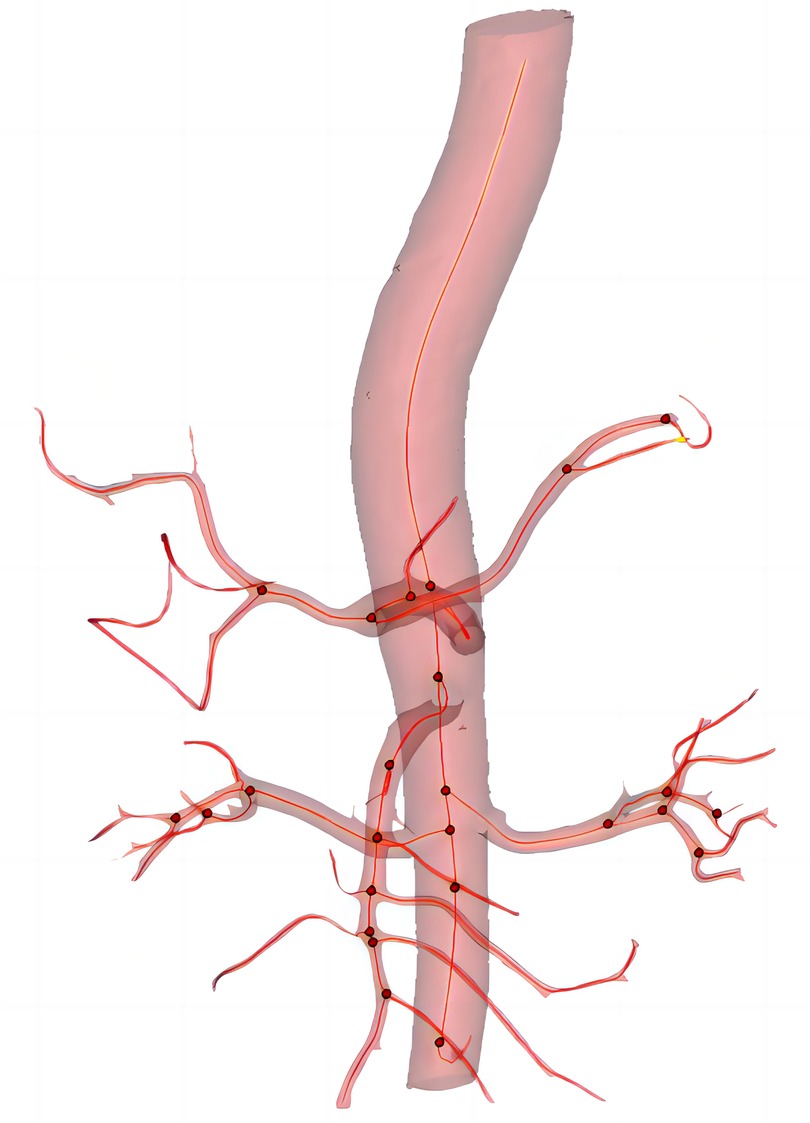

Measurement of anatomic data

In this study, all anatomical parameter measurements were performed using Materialise's interactive medical image control system software (Materialise, Plymouth, Mich). The specific method is as follows: the patient's CT images are imported into the MIMICS software system for the reconstruction of the aorta and its main branch arteries. Using the diameter measurement tool provided by the software, measurements are taken while delineating the centerline of the arterial lumen. The curvature and curvature are measured along this centerline (Figure 2). All reconstructions and measurements were performed individually by two researchers.

Figure 2. The three-dimension reconstruction of image and center line (red line), red dot indicates the presence of branched artery.